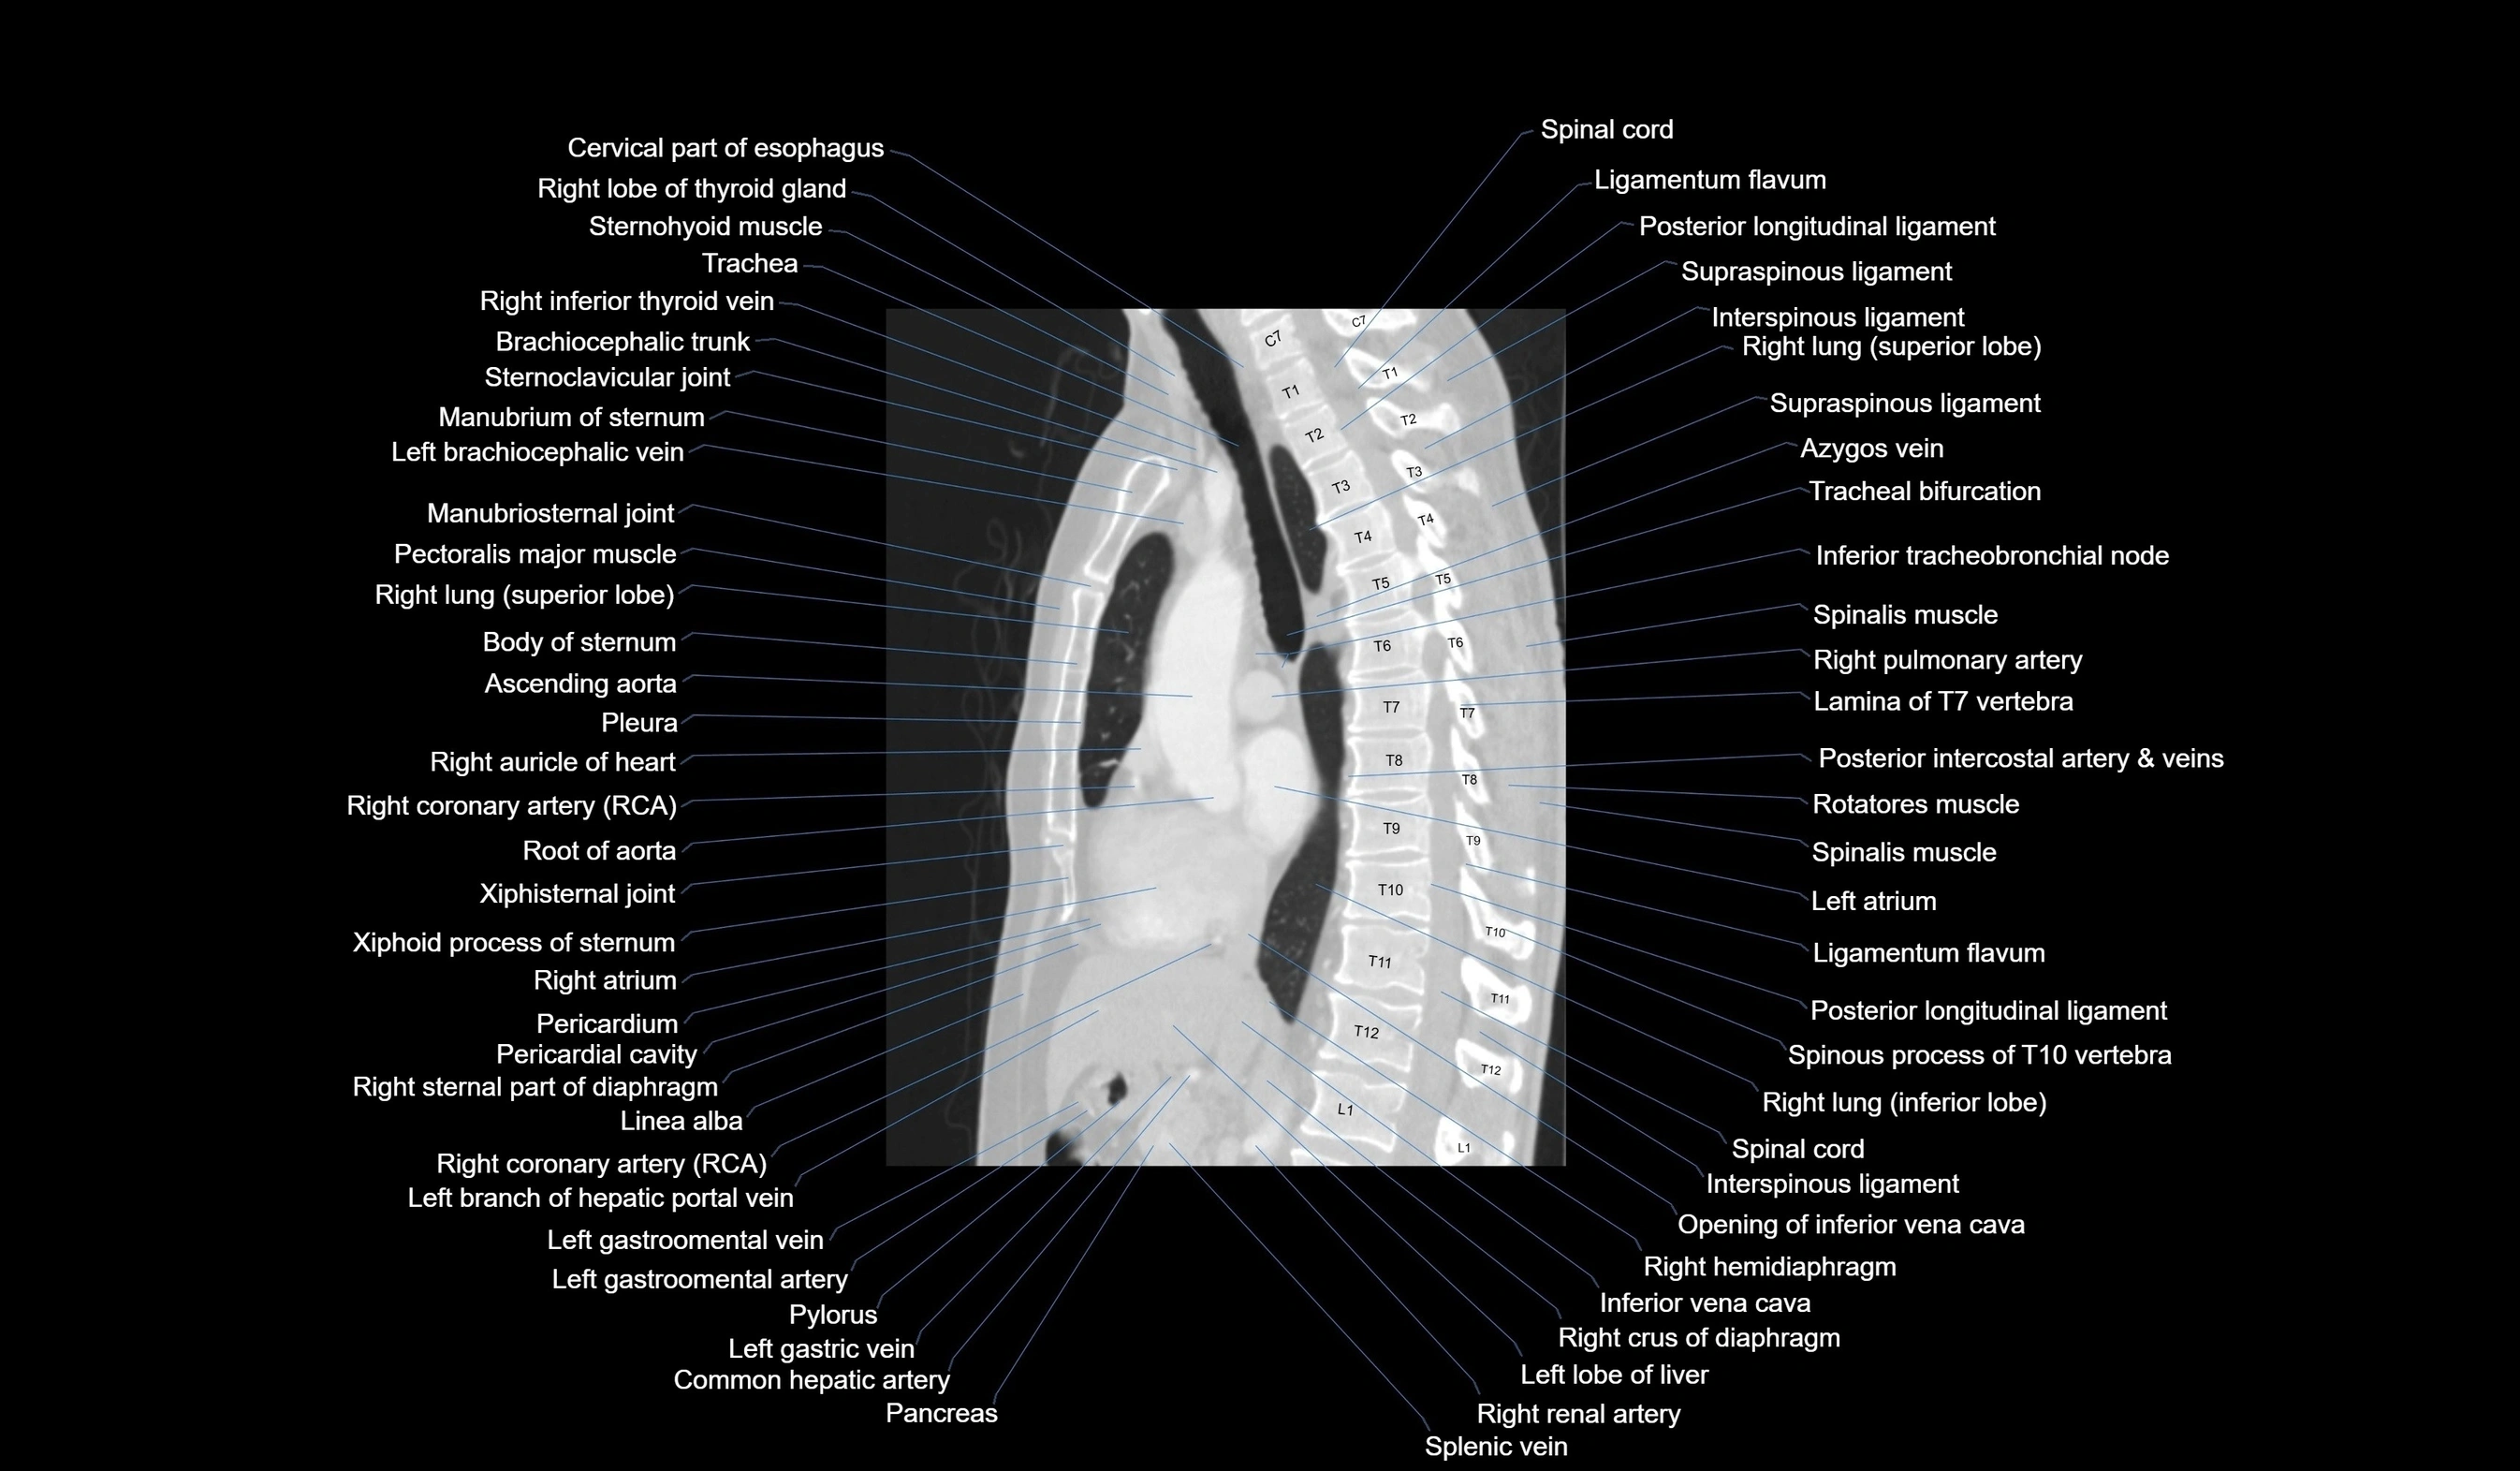

CT images